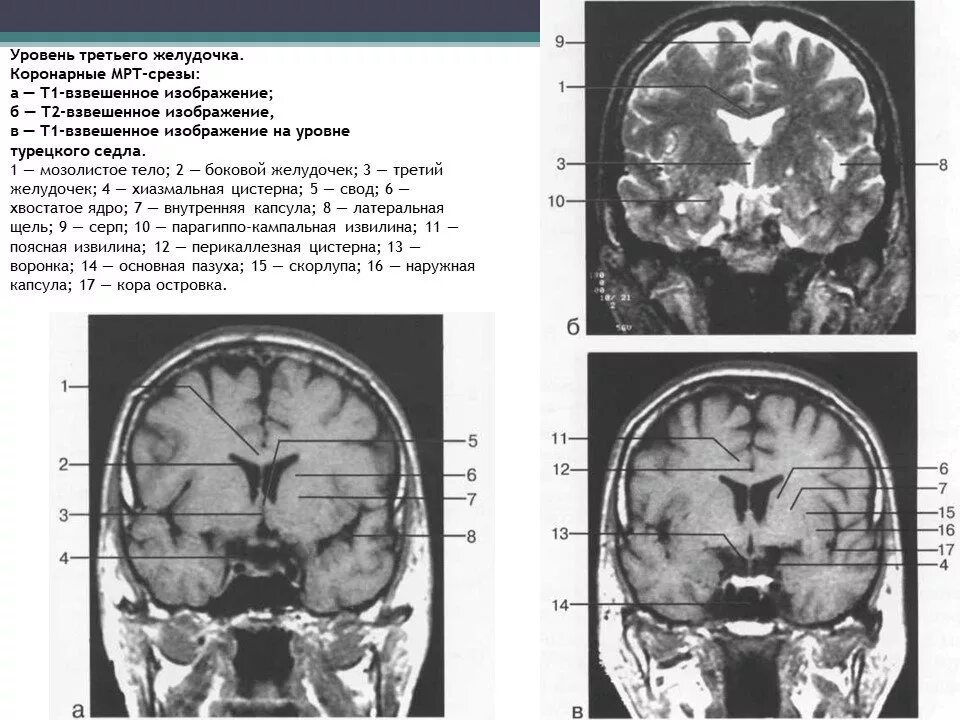

Атлас кт мрт